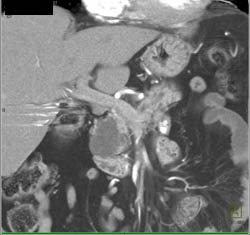

Diagnosis

Intraductal Papillary Mucinous Neoplasm (IPMN)